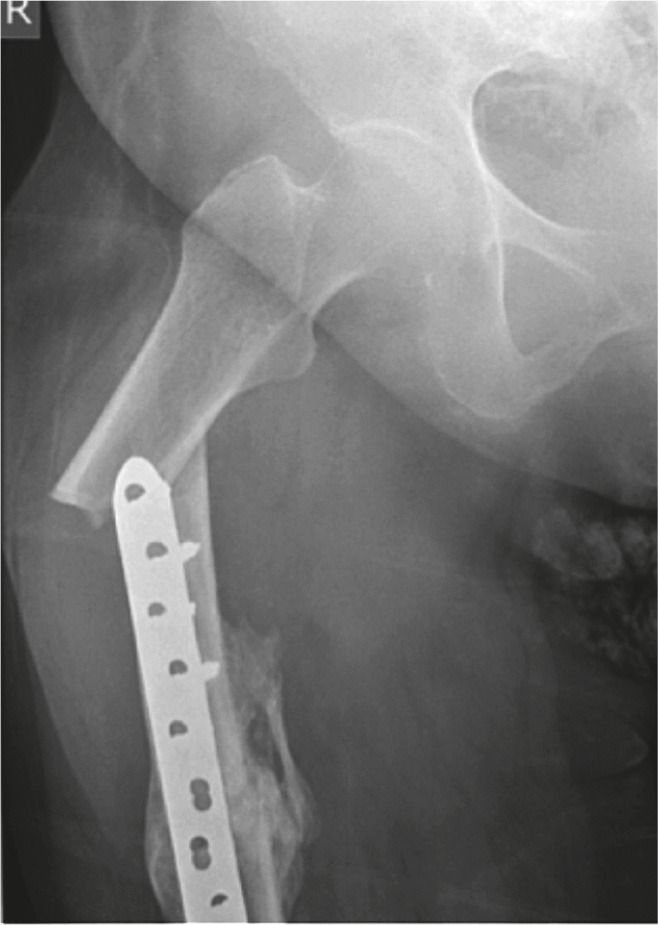

Figure 2.

Patient 5. Atypical peri-implant fracture at the proximal end of a plate used to fix a midshaft fracture of the femur.

In 8 of the injuries, the fracture line was at or just beyond the tip of the plate (Figure 2). In 3 of the injuries, the fracture was sustained through the second-most proximal screw hole of a plate. In 2 of these cases, the penultimate screw hole was the last functioning screw hole at the end of the plate (Figure 3). The fractures showed some radiographic features of atypicality such as (1) thickening of the lateral femoral cortex, (2) simple transverse or short oblique fracture pattern, and (3) absence of comminution.